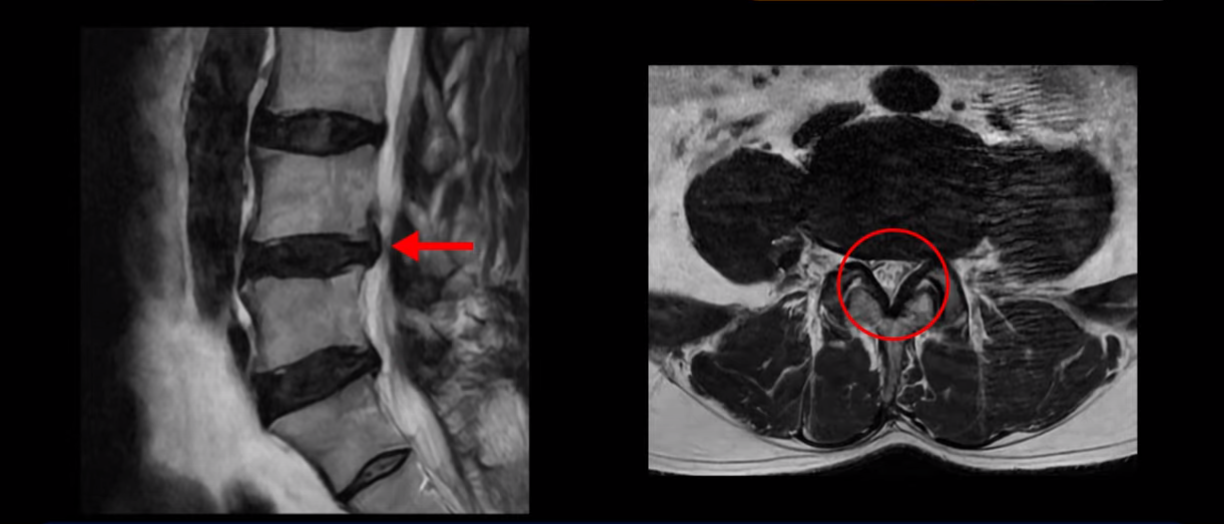

이분 MRI를 보면 허리 세 마디 정도의 퇴행성 디스크가 있고

4번 5번 마디에는 중심성 협착이 있습니다.

후관절과 황색인대가 두꺼워져 있어서 척추관이 좁아져 있습니다.

하지만 이분의 갑작스러운 통증을 일으키는 원인은 4번 5번에 발생한 디스크 파열입니다.

이분은 왼쪽 무릎 아래로 본인 표현으로는 다리를 잘라 버리고 싶다고 할 정도의 심한 통증이 있는데 보통 이런 표현은 디스크 파열이 발생했을 때 많이 사용하는 표현입니다. 이분 4번 5번 디스크를 자세히 보면 왼쪽으로 파열되어 밀려 올라간 디스크 수핵을 볼 수 있습니다.

옆에서도 보이지만 단면에서도 왼쪽으로 심하게 밀려나온 수핵이 잘 보입니다.